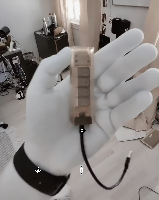

Мобильный рентгенаппарат + оцифровщик. Получение рентгеновского изображения на экране ноутбука. Вариант за 1,4 миллиона рублей под ключ.

Мобильный рентгенаппарат с печатью рентгенограмм на рентгеновской пленке. Цена 700000 рублей.